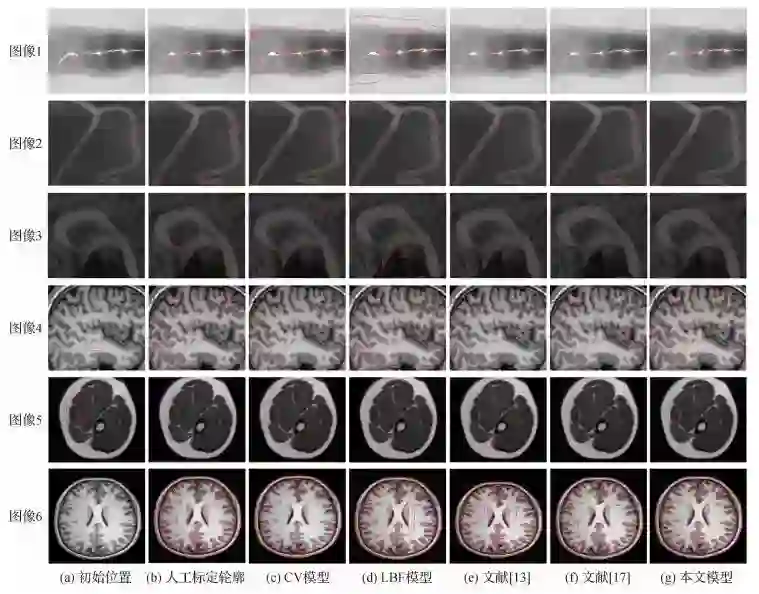

题目:结合分数阶微分和图像局部信息的CV模型

作者:张桂梅; 陈兵兵; 徐可; 储珺

单位:南昌航空大学

▲  不同方法的分割结果

引用格式:张桂梅, 陈兵兵, 徐可, 储珺. 结合分数阶微分和图像局部信息的CV模型[J]. 中国图象图形学报, 2018, 23(8): 1131-1143.